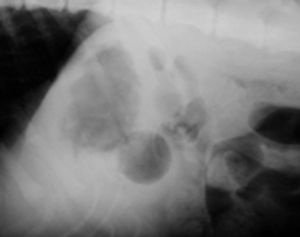

A 9-month-old intact male Labrador retriever was presented two weeks after it swallowed a Ping-Pong ball.